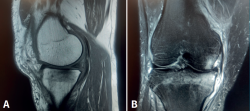

Figura 6. Resonancia magnética de rodilla, secuencias potenciadas en T2. A: corte sagital; B: corte axial. Se aprecia intenso edema óseo en el cóndilo femoral externo, con señal hiperintensa, e imagen de fractura trabecular subcondral como una línea hipointensa paralela a la superficie articular (flecha).

El origen traumático es la causa más frecuente de edema óseo. El impacto directo sobre el hueso subcondral puede generar fracturas trabeculares, que se presentan como imágenes lineales paralelas a la superficie articular, hipointensas en T2 (Figura 6). Se han descrito diferentes patrones de distribución del edema óseo, según el mecanismo traumático: